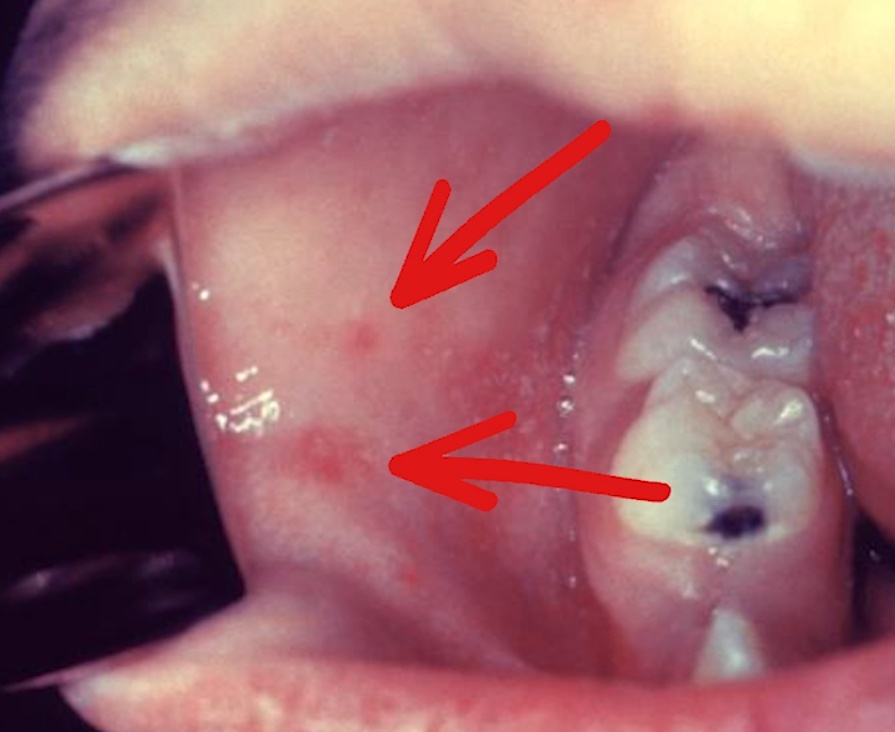

"4 C's of prodrome (early symptoms) = Cough, Coryza, Conjunctivitis, Koplik Spots"

blue and white candies: Koplik spots = bluish white spots on buccal mucosa